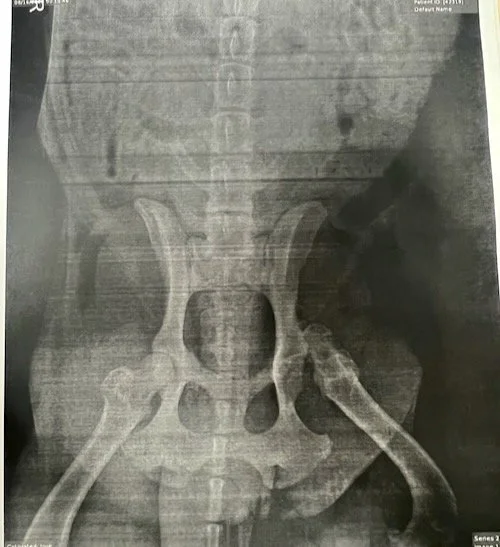

Champ’s Left Hip Socket Dislocation

X-rays revealed that his left hip was completely unhinged, with the ball of his femur dislodged from its socket. Was he hit by a car? Abused? We'll never know for sure. Champ went back in for more surgery. The FHO procedure removed the ball of his femur, allowing his leg to naturally reposition itself back into the socket. Scar tissue developed around the joint, securing it in place, and with time and effort, Champ's life would be allowed to continue with minimal change.